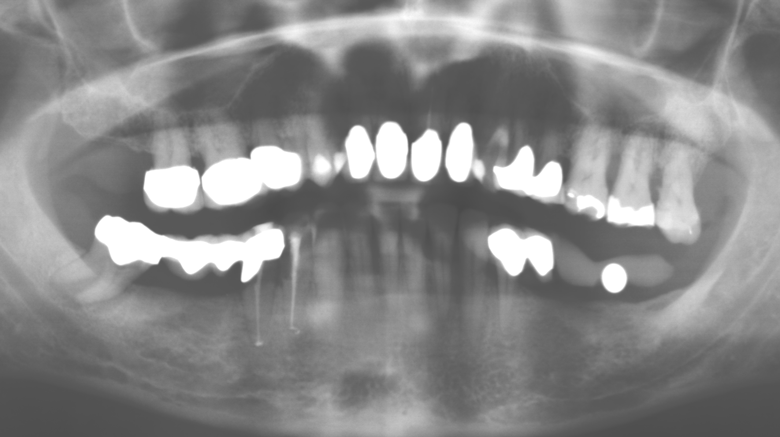

Standardised and regular risk-adapted care in the scope of SPT is the key to treatment success for the clinical long-term success in periodontically compromised patients. This is particularly true for patients fitted with implants following successfully completed periodontal treatment (Fig. 11a and b).

The ten-year check-up revealed no indications of advancing clinical attachment loss or peri-implant bone substance loss (Fig. 3).